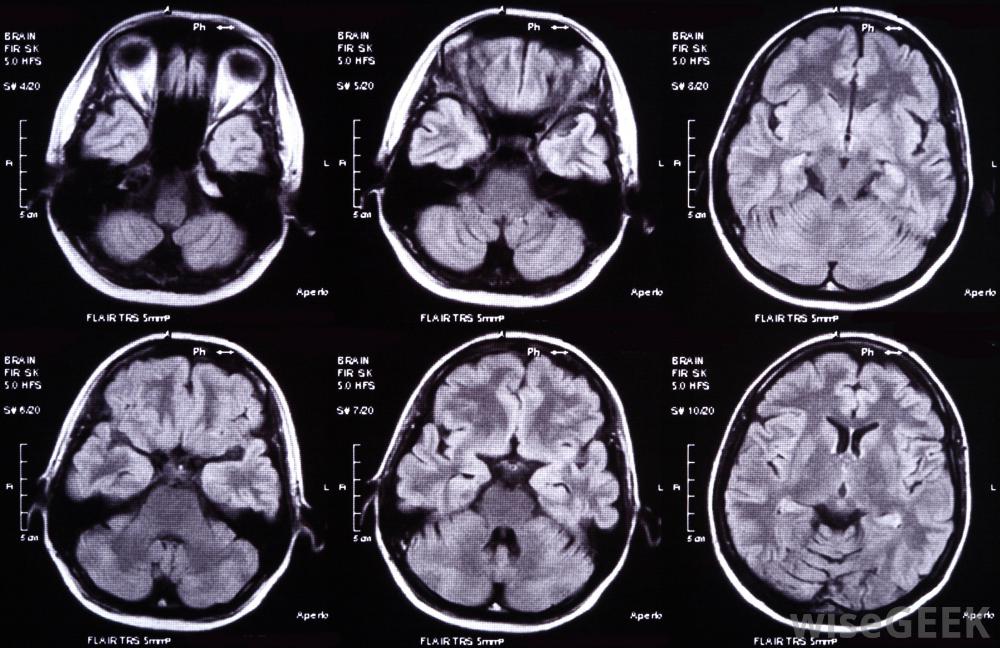

功能磁共振成像仪在个人进行活动或锻炼时实时捕捉大脑图像一旦进入功能磁共振成像机器,受试者可能会被要求听特定的声音,执行任务和认知活动,例如回忆过去的事件或执行需要某种推理的精神任务。然后机器就能绘制出大脑对这些任务的反应图。与脑电图(EEG)不同,这是一种研究和测量大脑内电流的技术,功能磁共振成像机能够记录大脑各个区域的活动。图像具有高分辨率,精度可达1毫米。扫描结果被广泛用作认知科学界的绘图和大脑分析工具磁共振成像(MRI)扫描的是身体结构的图像,而功能磁共振成像(fMRI)扫描通常是对代谢活动和功能的成像。代谢功能是指维持生物体生存所需的所有过程,例如,将食物转化为能量。功能磁共振成像机产生的图像能够真实地观察人体结构内部的代谢活动。这些设备并非毫无争议,因为它们有时会产生假阳性。当扫描结果产生"阳性"结果而事实上恰恰相反时,就会出现这种情况是真的。